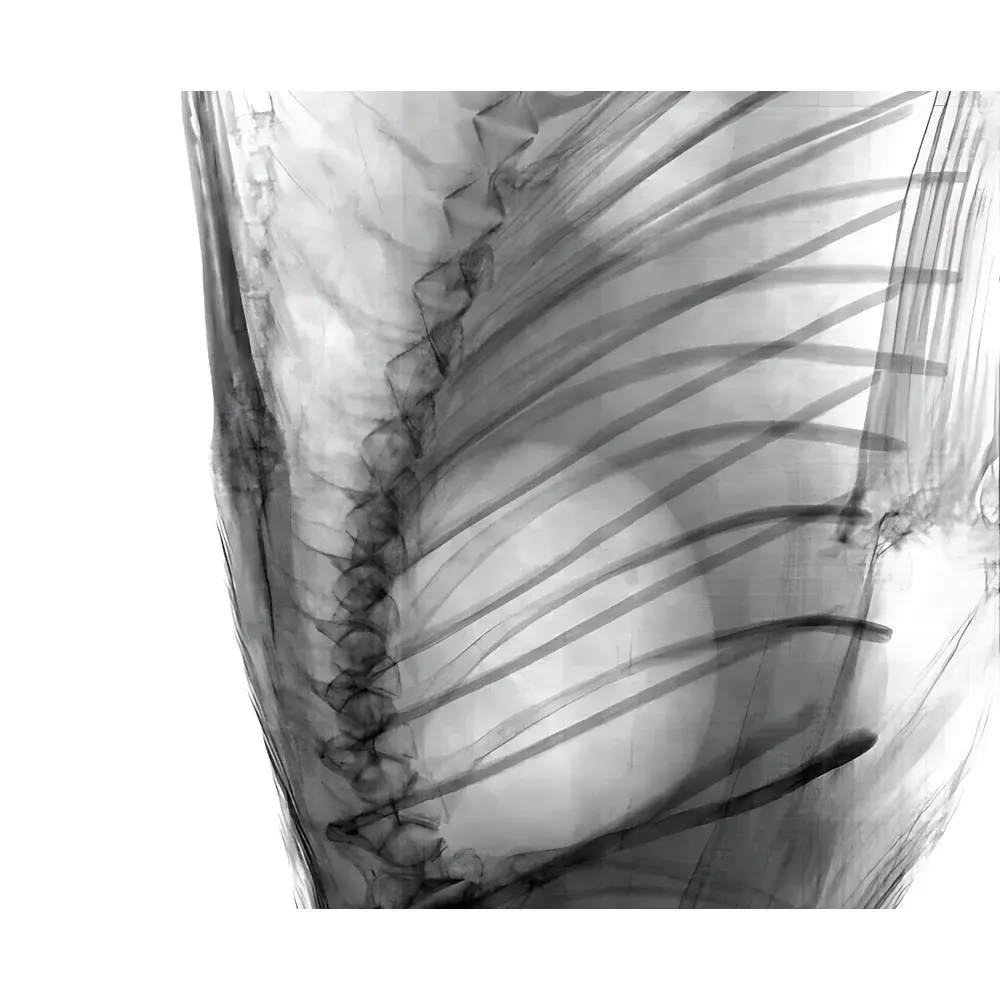

The AoLong Lab-Specific In Vivo Micro-CT Imaging System is a benchtop preclinical computed tomography platform engineered for non-invasive, high-resolution three-dimensional structural imaging of live small animals and biological specimens. Based on cone-beam X-ray microtomography (CBCT), the system delivers quantitative volumetric data without requiring tissue sectioning or contrast agent administration in many applications. It operates across a tunable tube voltage range (20–90 kV), enabling optimization for diverse sample densities—from soft tissues to mineralized structures—while maintaining sub-3-µm spatial resolution under optimal acquisition conditions. The system is purpose-built for longitudinal studies in pharmacology, oncology, orthopedics, and developmental biology, where repeated in vivo measurements must preserve animal viability and experimental integrity.

- Quantitative osteoporosis modeling: trabecular architecture analysis, cortical thickness mapping, and fracture risk simulation.

- Pulmonary airway remodeling in asthma and COPD murine models.

- Ex vivo validation of histological findings through co-registered virtual sectioning.